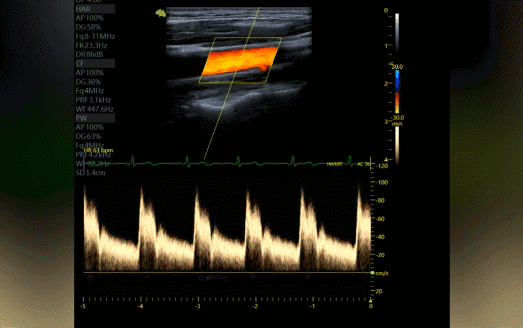

AMAS整体动脉僵硬度自动测量系统

对于中老年人,以及三高人群来说,心脑血管疾病的预防至关重要,每年的超声检查必不可少。

在检查过程中,除了观察血管的血流情况、斑块状态以外,检测主动脉脉搏波速度评估动脉僵硬度既是重点也是难点。

为此,飞依诺联合超声专家研发出简而有效的AMAS系统,操作者只需打开系统,一键点击,即可自动完成测量计算,轻松获得Aortic PWV指标,与传统操作相比可节约70%的时间。

飞依诺彩超图像